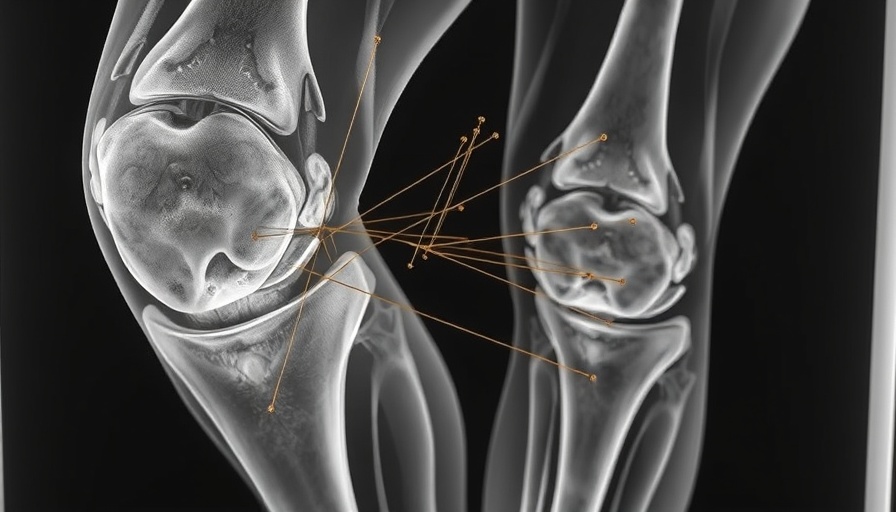

A 65-year-old woman from South Korea recently faced a medical conundrum that highlights the complexities of diagnosing joint pain. After a history of osteoarthritis in her knee, she sought various treatments that included painkillers and steroid injections, none of which provided relief. Consequently, she turned to alternative therapies, including weekly acupuncture sessions. Although acupuncture is known for its pain-relieving properties, this particular case took an unexpected turn when an X-ray revealed a shocking discovery: tiny golden threads embedded in her knee.

The tiny flecks visible in the woman's knee joint were identified as gold threads, intentionally inserted during her acupuncture treatments. Practiced primarily in Asia for conditions like osteoarthritis and rheumatoid arthritis, gold-thread acupuncture aims to provide lasting stimulation to the affected areas. However, as interesting as it sounds, this modality remains contentious. Despite its popularity, evidence supporting the efficacy of gold-thread acupuncture is largely absent. In some instances, reliance on such treatments has been correlated with worsened arthritis outcomes due to delays in seeking conventional medical care.